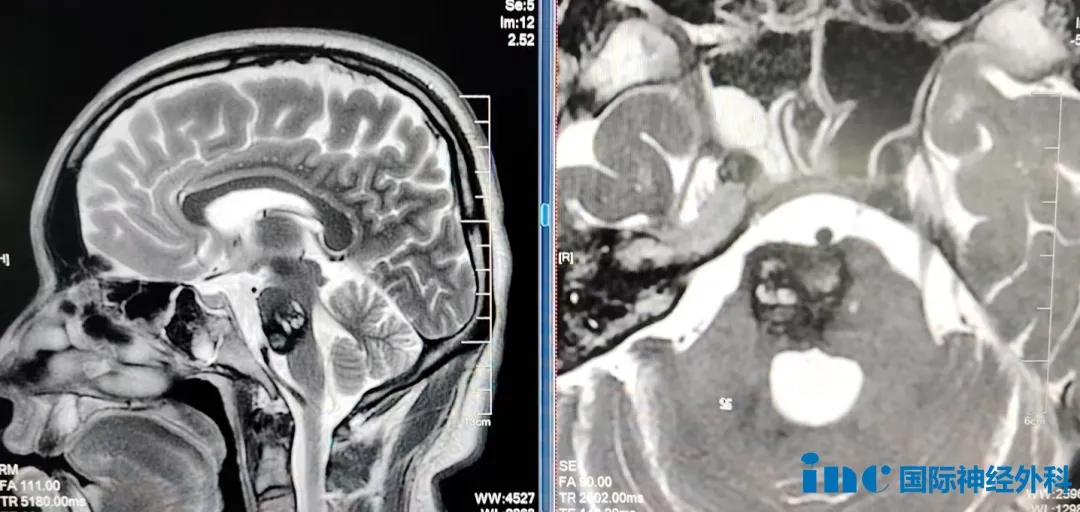

第二位患者是27岁的宇轩。熬夜后出现头痛,就医后发现脑干出血。住院后接受了保护性气管插管治疗,随后又紧急转院,转入抢救室。宇轩的病情持续危重,随后转入NICU进一步监护治疗。医院诊断为海绵状血管瘤伴发育性畸形,认为具有明确的手术指征,但同时告知:脑干手术治疗风险极高。宇轩目前左手、左脚无力,还出现左侧面部及颈部麻木,随后又进展至口唇麻木。其父母向巴教授表示:"您能给孩子做这台手术,我们感到非常幸运,我们就这一个孩子,希望巴教授您能救救我的孩子,太感谢了!"这台手术同样由巴教授主刀,顺利完成了全部操作。